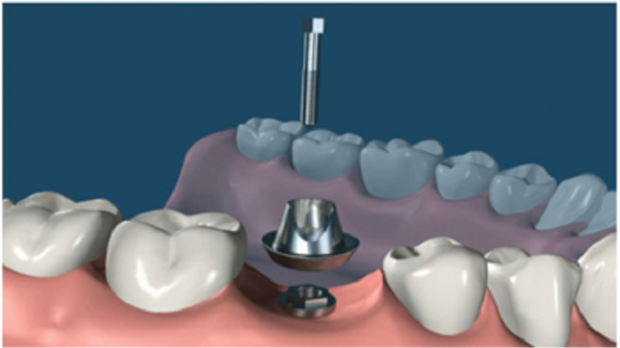

6. 安裝基臺(tái):骨愈合后就可以進(jìn)行二期手術(shù)使種植體穿出牙齦,為了幫助牙齦軟組織更快的愈合,會(huì)通過手術(shù)把種植體的覆蓋螺釘取替換成愈合螺釘。

7. 覆蓋義齒:兩至三周待軟組織成型后,就可以把愈合基臺(tái)換成基臺(tái)佩戴種植牙冠了;至此種植牙全部流程都已全部完成。